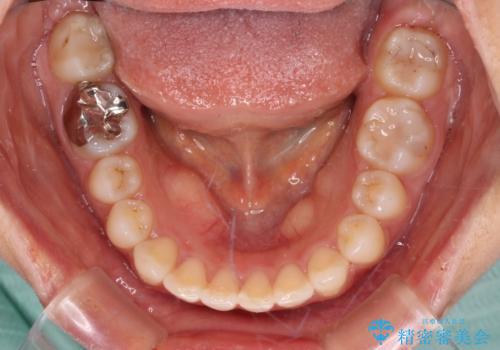

上下ともにデコボコの程度は著しいものではなく、インビザラインで十分に対応可能な歯列不正でした。

後戻りによりスペースができてしまうことを避ける目的で、IPR(歯と歯の間を削る)を極力用いない矯正治療を行うこととしました。

インビザラインであれば来院間隔が多少長くなってもワイヤー矯正ほど問題とならないため、遠方からの通院であっても中断や転院せずに治療を行うことができます。